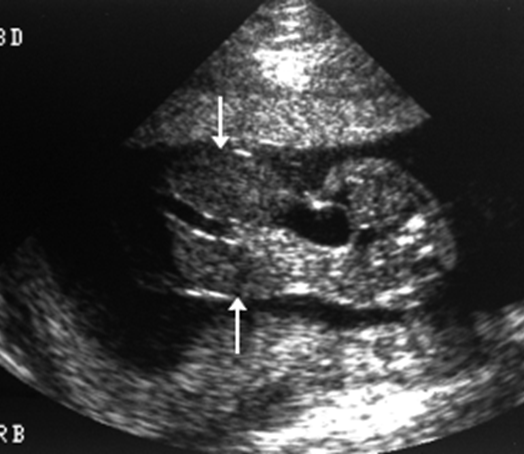

CDH